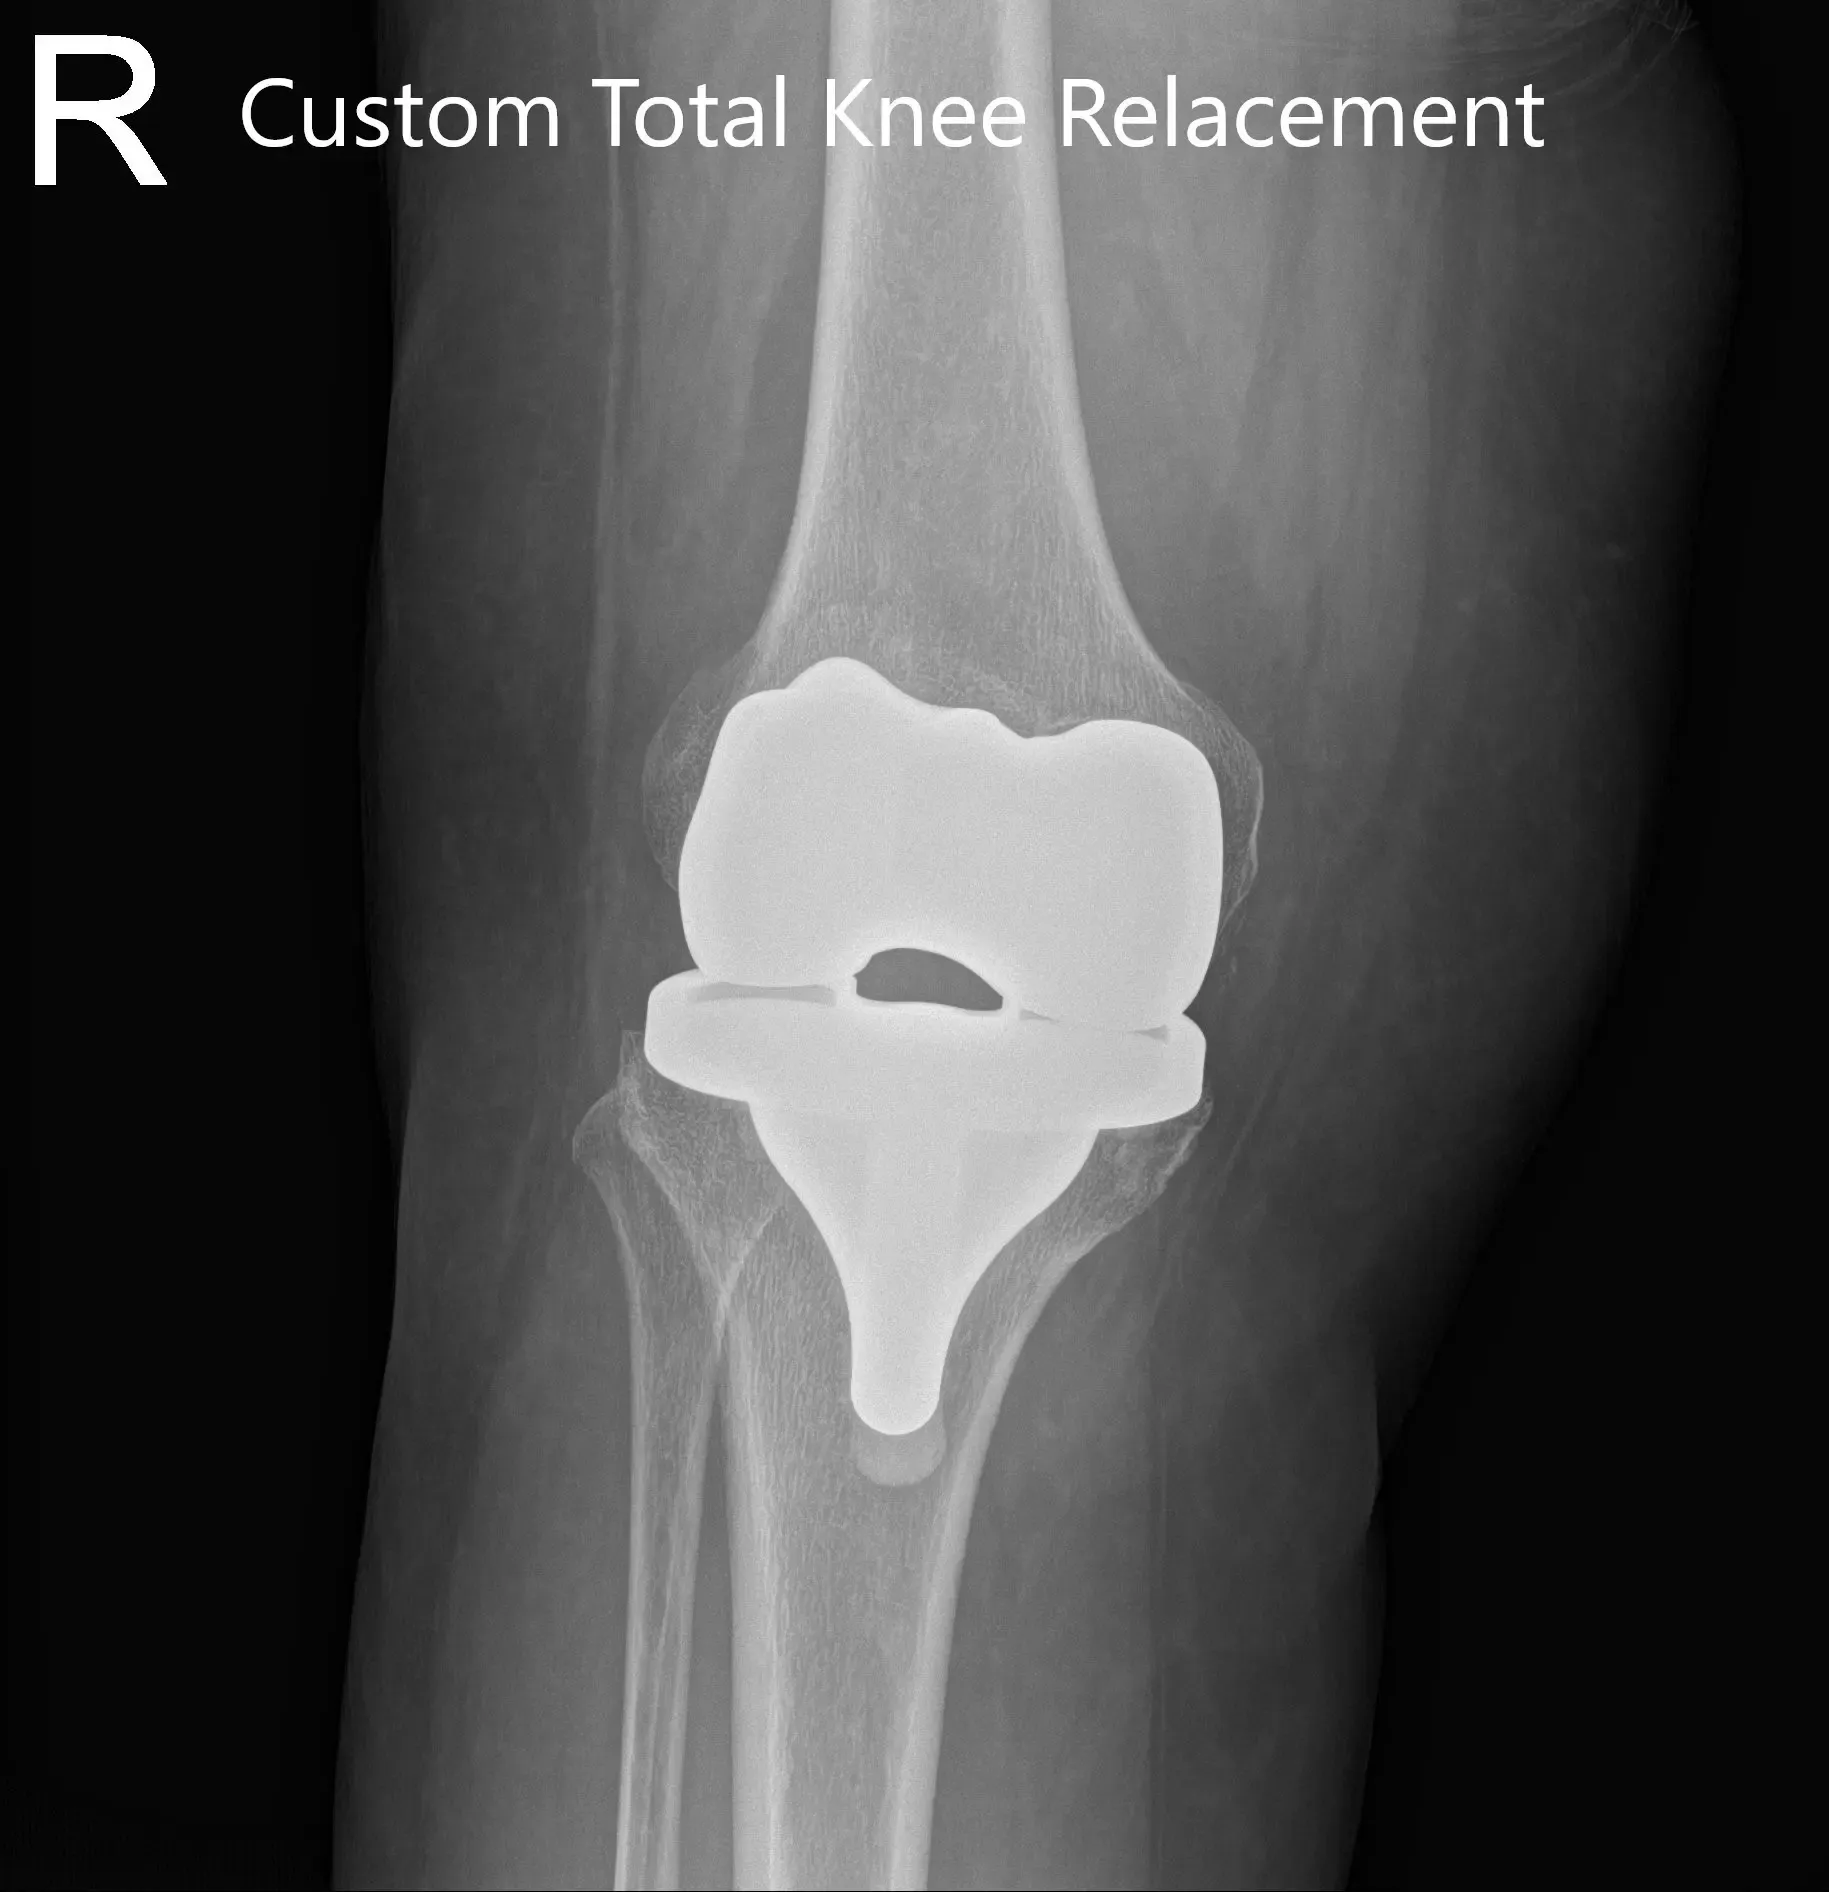

OPERATION: Right total knee arthroplasty using custom femoral component with a custom tibial tray with polyethylene 6 mm with patella 32 mm x 6mm.

Postoperative X-ray of the right knee showing AP and lateral views